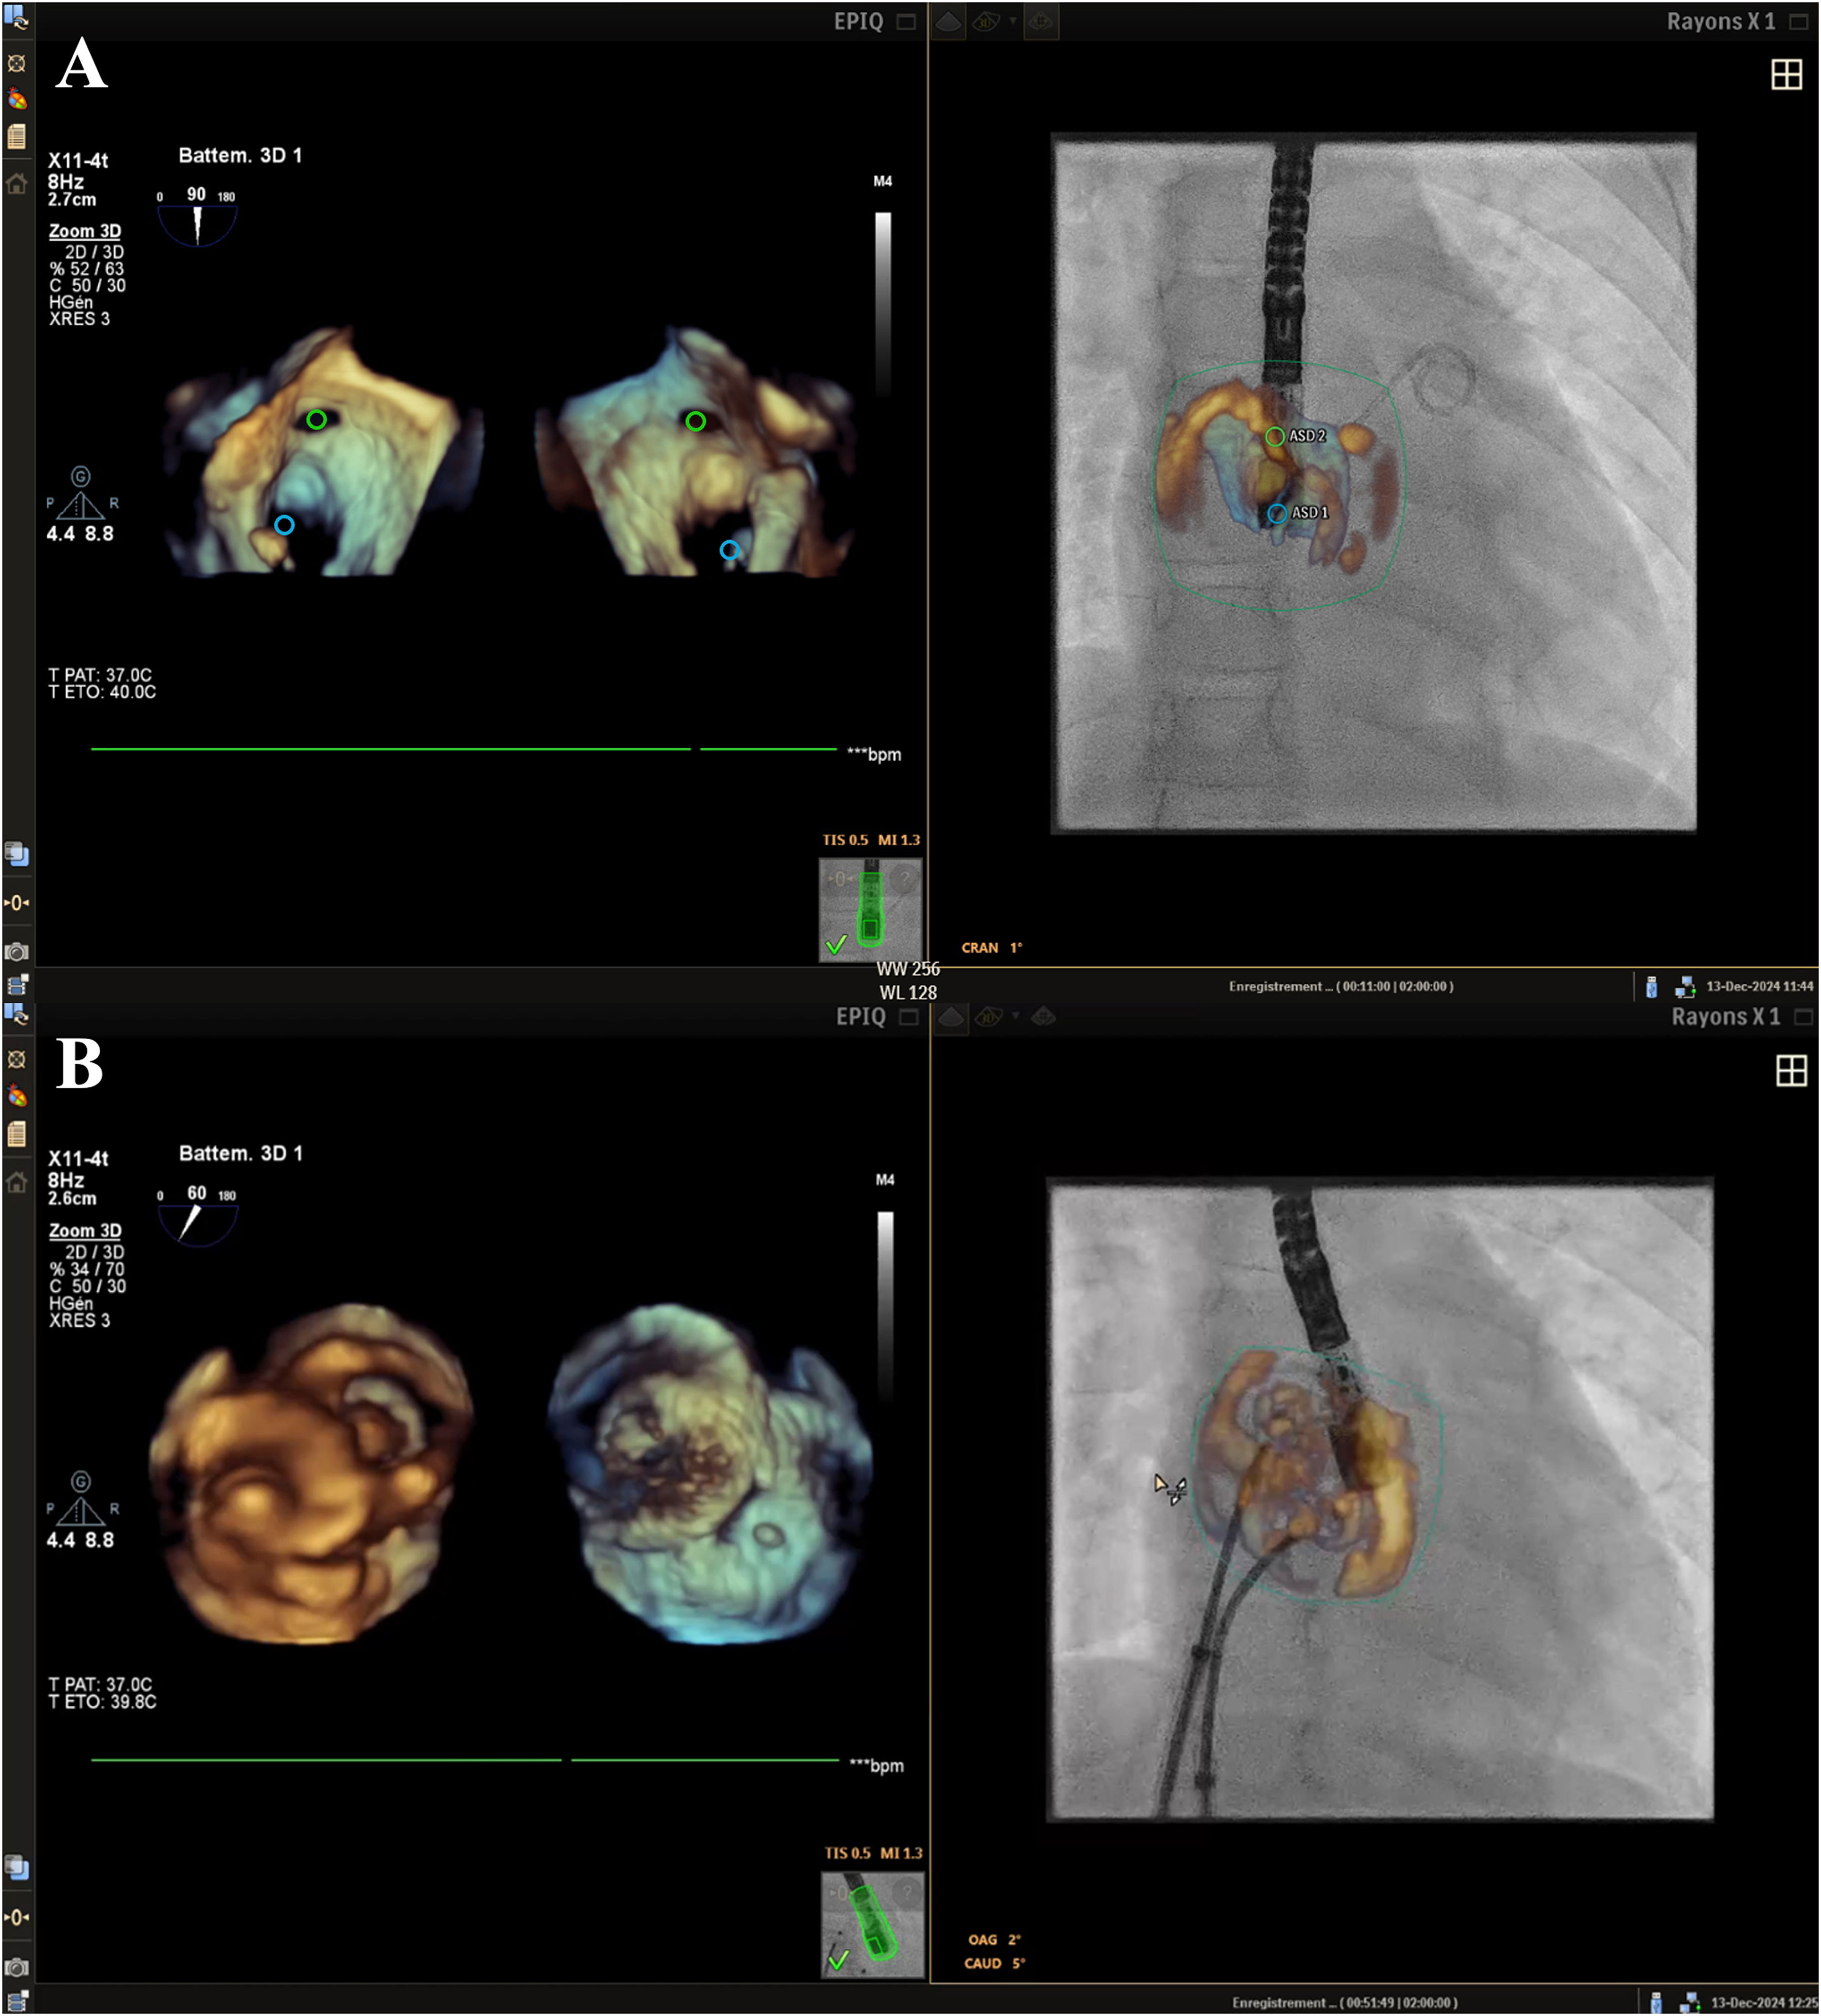

EFF imaging was successfully performed in all 8 ASD cases, and in 1 patient with a complex separated double ASD, EFF imaging offered enhanced guidance for crossing both defects separately, enabling improved manipulation and repositioning of the prosthesis, as well as the simultaneous deployment of 2 ASD occluders (figure 1A,B). EFF imaging was also successfully used in all 10 cases of VSD, enabling assessment of the size, position, and rims of the defects. EFF imaging also facilitated precise VSD crossing using markers (figure 2A) and ensured accurate prosthesis placement (video 1 of the supplementary data). In the case of a 2-year-old patient with congenitally corrected transposition of the great arteries with dextrocardia, a complex diagnostic catheterization was performed guided by EFF imaging. Given the atypical cardiac anatomy and spatial orientation, which complicates visualization and interpretation and the mirrored positioning of the heart and associated structures, EFF imaging played an important role in helping the interventional cardiologist understand the anatomy and the spatial orientation to better guide the catheterization procedure (figure 2B, video 2 of the supplementary data). EFF imaging was also successfully employed for an atrioseptostomy in a 3-year-old patient with nonoperated corrected transposition of the great arteries and VSD.

Three-dimensional echocardiography-fluoroscopy fusion (3D EFF) imaging during atrial septal defect (ASD) closure in a 17kg patient. A: 3D transesophageal echocardiography showing a face view of 2 markedly separated ostium secundum ASDs from the right atrium (left panel) and the left atrium (right panel). The pigtail crossing the largest defect is shown in both 3D and fluoroscopic images. B: 3D en face view of a 16-mm device (lower device) and a 12-mm device (upper device).